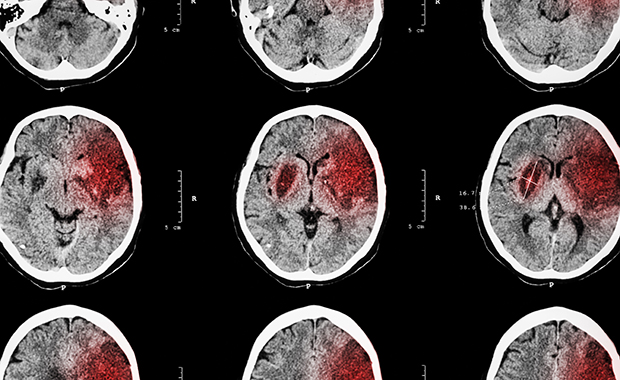

閉塞性睡眠時無呼吸症候群の患者さんについて調べた研究によれば、重症の人は脳血管が詰まる脳梗塞や、脳血管が破れる脳出血のリスクが、健康な人の3.3倍になることがわかっています。

脳梗塞が起こると、「手足がしびれて力が入らない」「言葉がうまく話せない」「ものの見え方がいつもと違う」などの症状が突然現れます。